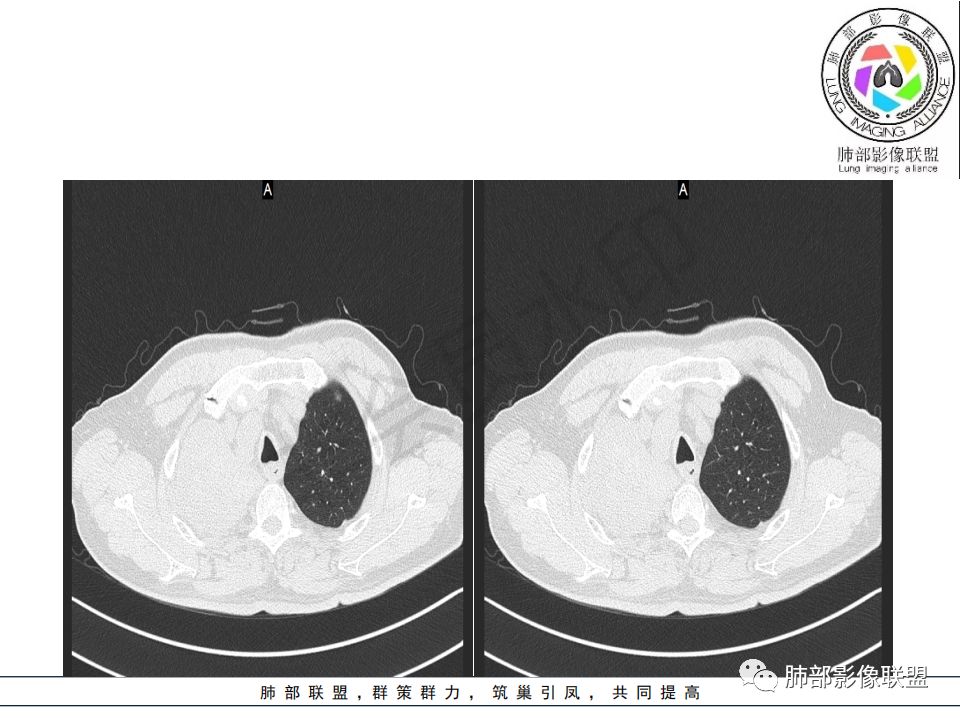

右肺主支气管有软组织肿块,向腔内外生长,右肺上叶肺不张,边缘光滑,增强扫描不均匀强化。考虑恶性肿瘤,鳞癌可能。

右肺主支气管内外软组织影,支气管变窄截断,右肺上叶成软组织密度,其内见细沙样钙化,周围看见小结节,右肺门看见一淋巴结稍大,增强不均匀强化,胃癌病史,考虑:转移,或原发肺恶性鳞癌。

晨读:患者老年男性,以咳嗽一月就诊,少量白痰,胸CT:纵隔右移,右肺体积缩小,气管下段管壁可见结节样改变,气管软骨变形,气管下段及右主支气管可见新生物向管壁浸润,并向管腔外生长,右上肺肺不张,但不张边缘可见病灶呈膨胀性生长,可见分叶,增强后强化明显。考虑:肺部恶性病变(鳞癌?)

晨读病例:老年男性,症状轻,右侧胸廓略塌陷,右肺主支气管内外软组织影,支气管变窄截断,右肺上叶不张,其内见细砂样钙化,周围看见小结节,右肺门看见一淋巴结稍大,增强不均匀强化,胃癌病史,常规考虑:转移,或原发肺恶性鳞癌。鉴别支气管TB?